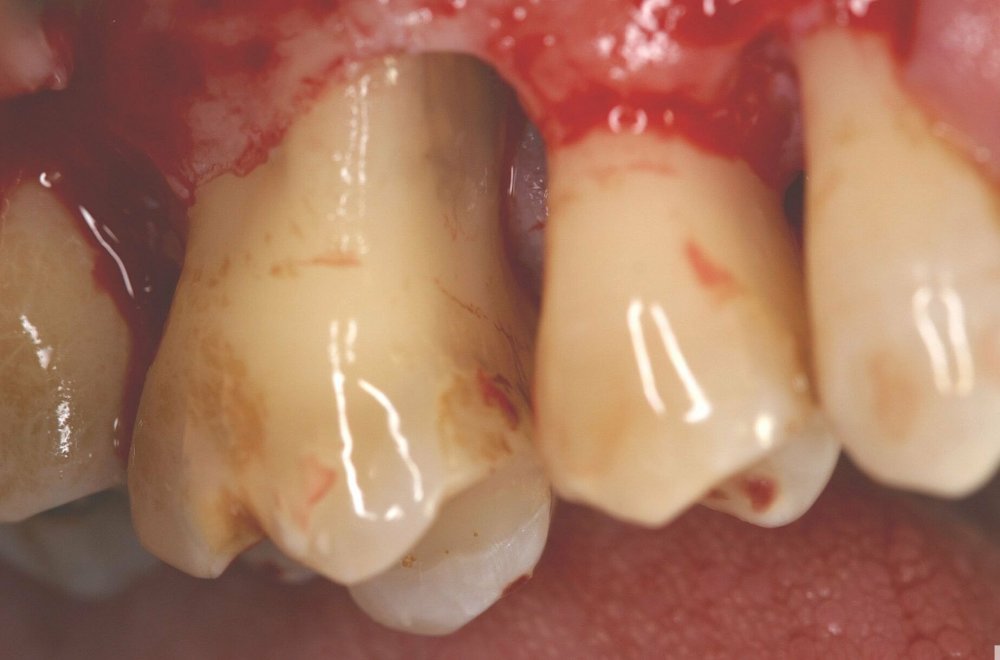

Qeyri-cərrahi parodontoloji müalicədən sonra bəzi hallarda, bu və ya digər bölgədə dərin parodontal ciblər (diş əti və sümük cibi) qalmaqda davam edir. Bu hallarda çox zaman müalicə cərrahi metodların tətbiqi ilə davam etdirilir. Bu zaman əsas məqsəd mövcud parodontal cibin bu və ya digər metodlarda aradan qaldırılmasını təmin etməkdir.

Çünki bu ciblər çox zaman pasiyent tərəfindən yetərincə təmizlənə bilmir. Bu isə həmin bölgəyə tədricən ərp və dolayısı ilə də bakteriya koloniyalarının toplanmasına səbəb olur. Bu proses yenidən yerli iltihabın ortaya çıxmasına səbəb olur. Tətbiq edilən cərrahi metodlar əsasən cibin yerləşdiyi diş bölgəsi, cibin eni, dərinliyi, konfiqurasiyası və s. xüsusiyyətlərə görə müəyyənləşdirilir. Bu zaman məqsəd mümkün olduqda həmin bölgədə bərpa prosedurunu həyata keçirmək, mümkün olmadıqda isə rezektiv müalicənin tətbiqi ilə həmin bölgəyə ərp toplanma ehtimalını azaltmaq və gigiyenik prosedurların icrasını pasiyent üçün rahatlaşdırmaqdır.

Rezektiv prosedurlar zamanı müəyyən miqdarda yumuşaq toxuma (diş əti), sərt toxuma (sümük) və ya kombinə olunmuş şəkildə (həm sümük, həm də yumuşaq toxuma) rezeksiya həyata keçirilir. Prosedur yerli ağrısızlaşdırma altında aparılır. Əməliyyatdan sonrakı dövrdə fərdi qulluq və gigiyena qaydalarının mötəxəssis tərəfindən izahı və müvafiq instruksiyanın verilməsi olduqca önəmlidir.